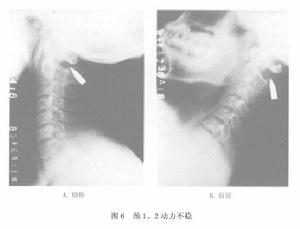

2.動力性不穩

主要因橫韌帶翼狀韌帶或齒狀韌帶及周圍關節囊等鬆弛與不穩所致者,除可查出明顯原因可歸於器質性不穩症外,其餘均屬此類 此種不穩除可引起前後向或側向(左右)不穩外(可分別從X線側位及正位片上判定)尚應注意因一側翼狀韌帶鬆弛所引起的鏇轉不穩。